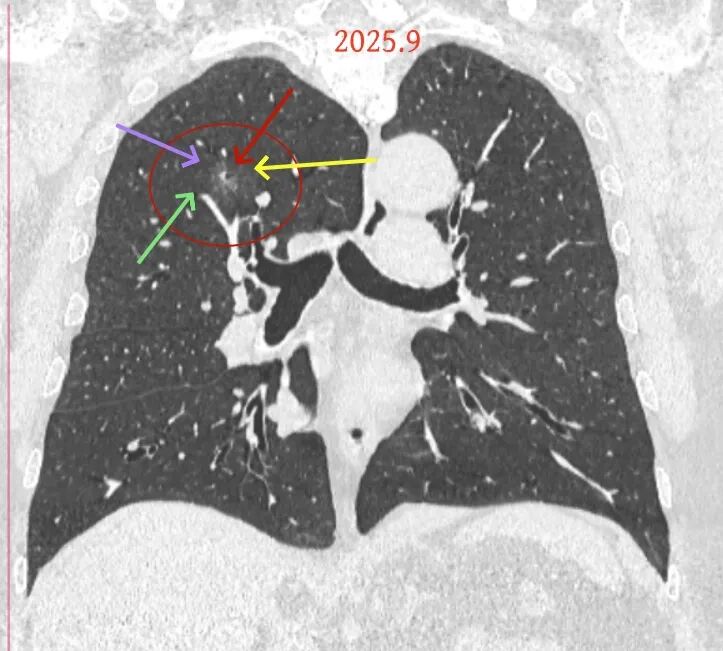

方形的是25年的,红色的主病灶,磨玻璃密度伴少许略偏高点密度,但还说不上典型混合磨玻璃病灶,考虑原位癌或微浸润性腺癌可能性大;蓝色的轮廓与边界欠清,位置靠上叶中央,无法段切或楔切;黄色的多发均淡而纯,分布在两肺。圆形粉色的是主要的两处23年时的样子,对比说不上很明显进展。鉴于若手术得切肺叶,何况两肺他处仍的结节,年纪又74了。我倾向保守点,先6-9个月复查,等进展并风险增加再来考虑怎么办的事。意见供参考!

病灶B似乎灶内有少许密度略偏高,但瘤肺边界欠清晰,总体说不上太显著的进展。

当时结友自己还觉得有点实性成分,血管感觉也有增粗。而我觉得整体密度仍是磨玻璃,轻微的变化仍不足以影响临床决策的程度。

病灶没有确切纵隔窗可见的实性成分,但与血管关系较为密切。